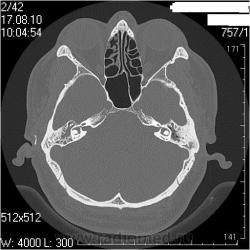

Соглашусь с Виталием. Мы делаем височные кости отдельными реконструкциями на правую и левую кость еще по 0,6мм. Здесь не знаю как, но вот по 0,6мм (кстати, так делают в Европе, насколько мне известно) плотность померить - результаты будут от фонаря. И еще мне режет уши - заполнено патологическими структурами. Что за структуры? Андрей Юрьевич, это Ваше описание? Я видел подобные в ММА Сеченова. вообще, мне нравится такой тип описания, когда все четко по полочкам разложено, не надо заниматься, порою, долгим поиском интересующей области в тексте описания. Кстати, достоверного блока устья левой трубы не вижу на представленных томограммах. Похоже, просто не те срезы выбраны. (сразу скажу, я не спец по ушам , хочется разобраться) Вернее сказать, вообще не вижу блоков. Покажите, если не трудно

Андрей Юрьевич, про размеры... Пишите, что размеры в пределах нормы, затем указываете параметр и норму, в которую этот параметр не укладывается. Или я что-то не так понял?

А засада (что НЕ ТАК), для меня здесь вот в чем. У пациента клиника левостороннего отита (многолетний анамнез, отделяемое из уха, перфорация перепонной барабанки при отоскопии), а справа клиники нет совсем. После КТ ЛОРы дописали рубец на правой перепонке, и выписали + с адгезивныи отитом справа (хотя при адгезивном отите КТ-картина должна быть несколько иная).

А сижу и думаю, чтож это было-то, и правильные ли я сделал выводы? Или тут тоже действует этот радиологический перл : Sinusitis is a clinical diagnosis. Sinus images frequently bear no relationship to the patient's symptoms. - Синусит-это клинический диагноз. То что мы иногда видим в синусах, зачастую не имеет никакого отношения к симптомам которые испытывает исследуемый нами пациент. Richard H. Daffner MD, FACR. Professor of Radiologic Sciences. Clinical Radiology.